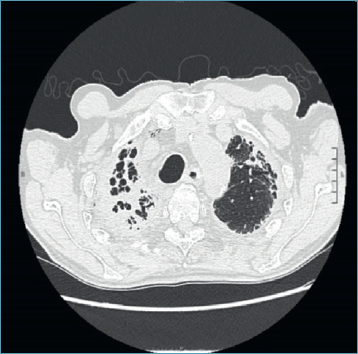

Il paziente arrivava pertanto alla nostra attenzione dopo avere già eseguito TC torace ad alta risoluzione (HRTC) e PET TC con 18 FDG. La TC torace mostrava la presenza di ispessimenti pleurici, associati a grossolane ed irregolari bronchiectasie in sede apicale bilaterale (Figg. 1 e 2). A latere, si riscontrava deviazione della trachea verso destra ed esofago toracico beante nel suo tratto intermedio. Dalle immagini radiologiche non risultava la presenza di versamento pleurico né pericardico. In associazione alla TC torace ad alta risoluzione, il paziente veniva sottoposto a PET TC con 18 FDG per lo studio metabolico delle placche pleuriche apicali; quest‘ultima, tuttavia, mostrava solo una debole captazione delle lesioni pleuriche apicali, non suggestiva di patologia oncologica.

Figura 1.HRTC torace: scansione assiale a livello dei lobi superiori.

Figura 2.HRTC torace: scansione coronale a livello della carena tracheale.